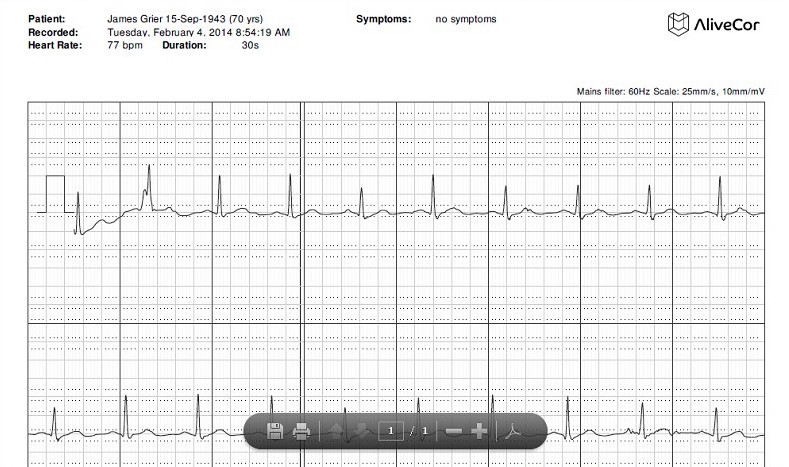

AliveCor

Чехол для мобильного телефона, который позволяет записывать ЭКГ. Довольно «громкий» проект, активно поддерживаемый прессой. Данные измерений остаются в памяти смартфона, их можно просматривать на компьютере. Также за дополнительную плату можно получить расшифровку кардиолога.

Измерения удобнее всего производить, приложив пальцы к контактам устройства. При этом «поменять» отведения можно, снимая замеры с груди или приложив чехол к ноге. В настоящее время ассортимент расширился, и пользователям предлагается купить отдельно «пластину» с контактами вместо чехла.